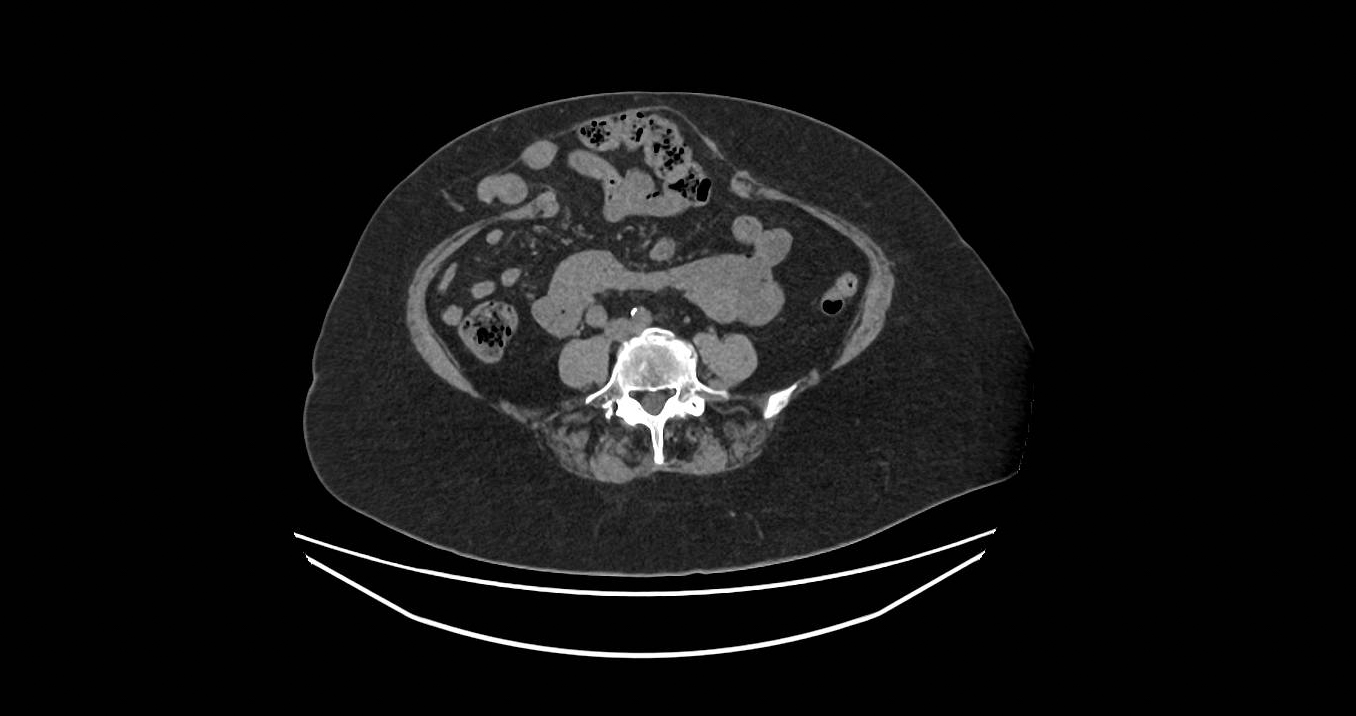

- CT scan

Uses x-rays